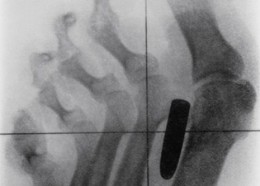

Чудни ренгенски снимки